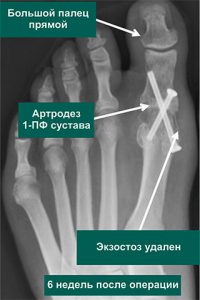

Вальгусная деформация пальца мкб 111 фотографий